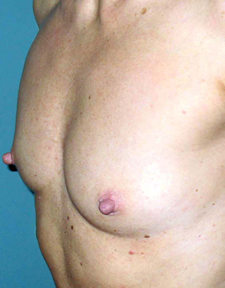

Les patientes de cet album ont des voies d’abord différentes, comme des tailles de prothèses ou de positionnement par rapport au muscle pectoral.